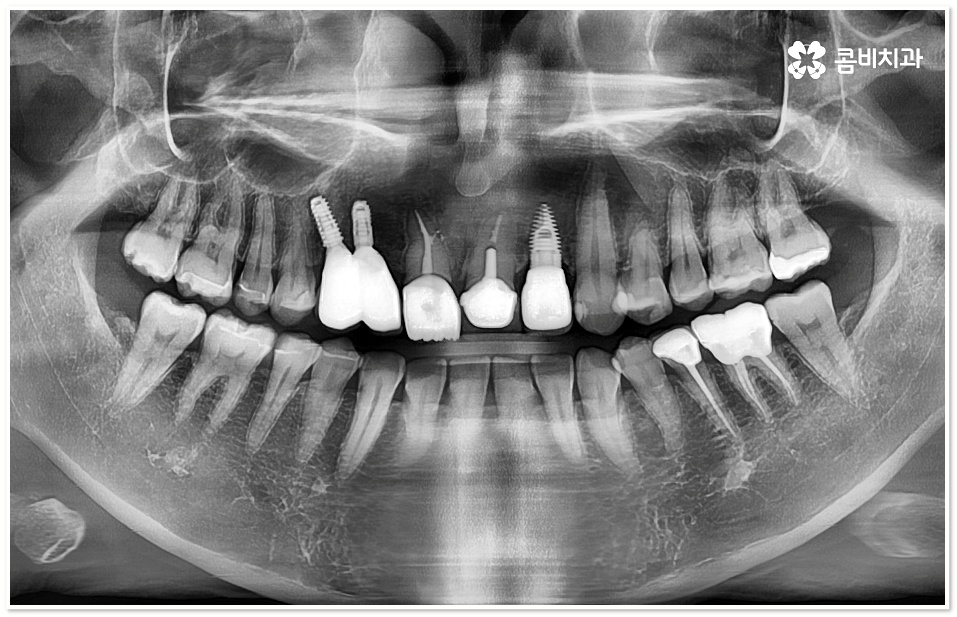

임플란트 시술은 상실된 치아를 대체하여 인체에 해가 없는 티타늄 소재로 된 인공치근을 잇몸뼈에 직접 식립한 후 기둥으로 인공치근과 인공치아를 연결하는 방식으로 진행되는데 앞니임플란트 시술을 받으면 씹는 힘도 자연 치아의 80~90% 가까이 회복할 수 있고 겉에서 보기에도 원래 자연 치아와 거의 흡사하게 수복이 되기 때문에 현대 임플란트 시술이 치아 상실을 대체하는 가장 대표적인 인공 치아 보철물로 자리매김 하고 있어요.

더욱이 앞니의 경우 말씀드린 것처럼 기능적인 부분 만큼 심미적인 부분까지 신경을 써서 주변 치아와 모양이나 색상, 투명도 등 모든 면에서 자연스럽게 어우러질 수 있는지 체크할 필요가 있기 때문에 앞니임플란트 시술이 어금니보다 까다로울 수 있어요.

앞니임플란트 시술은 담당의 선생님의 숙련도가 크게 영향을 미치는 고난도의 치과 진료인 만큼 임상 경험이 풍부하고 뛰어난 노하우를 가지고 있는 의료진과 충분한 상담 후 보다 안정성이 검증된 정품 재료를 활용하여 각자의 상태에 맞는 적합한 방법을 통해 무리하지 않게 식립 시술을 진행하는 것이 중요하며 또한 치과의 체계적인 케어 시스템을 통해 주기적인 사후 관리를 철저하게 받는다면 임플란트 치아의 장기적인 안정성과 수명을 높이는데 도움 받아 보실 수 있어요.